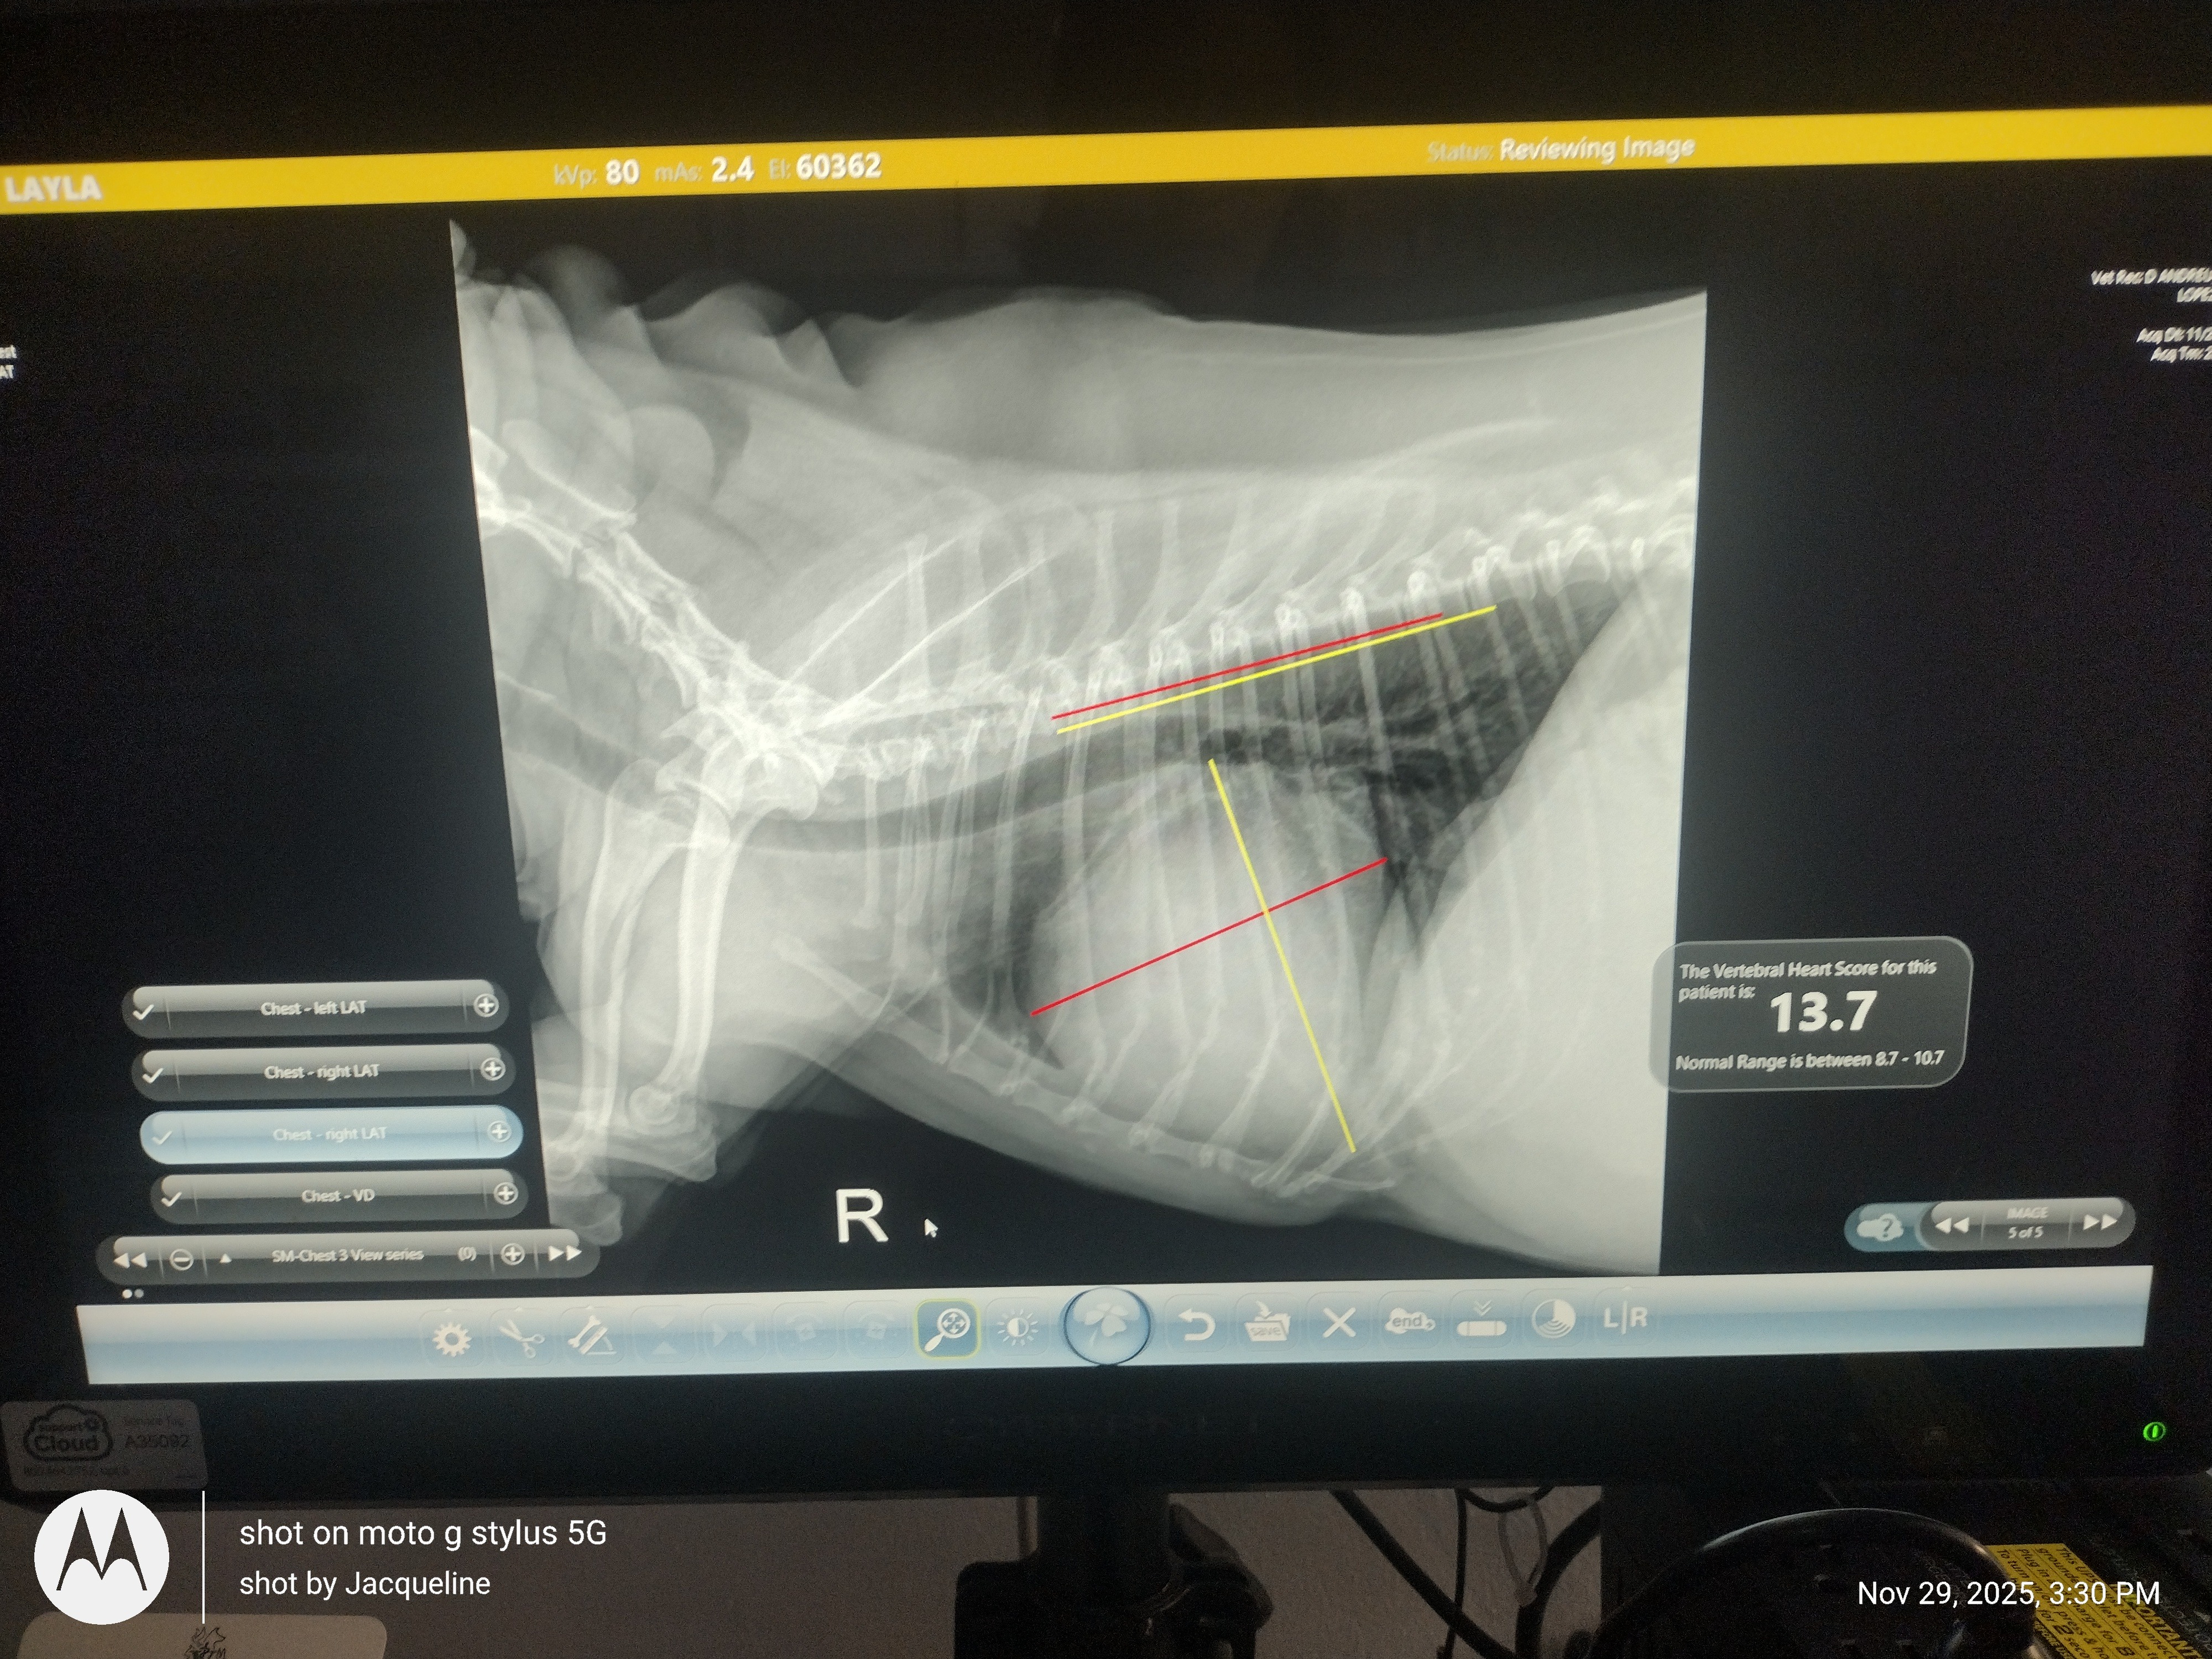

Now, at 13 years old, Layla is facing serious health challenges. She has been diagnosed with an enlarged heart, oral disease, arthritis, and pancreatitis. The vet says she needs an ultrasound or echocardiogram to address her heart before she can have the oral surgery she desperately needs. X-rays show her heart is pressing against her esophagus, causing her to cough. Lucy is on SSI, and almost all of her income goes to rent and bills. I am also on SSI due to illness, so together we simply cannot afford Layla’s looming medical costs.

Now, at 13 years old, Layla is facing serious health challenges. She has been diagnosed with an enlarged heart, oral disease, arthritis, and pancreatitis. The vet says she needs an ultrasound or echocardiogram to address her heart before she can have the oral surgery she desperately needs. X-rays show her heart is pressing against her esophagus, causing her to cough. Lucy is on SSI, and almost all of her income goes to rent and bills. I am also on SSI due to illness, so together we simply cannot afford Layla’s looming medical costs.